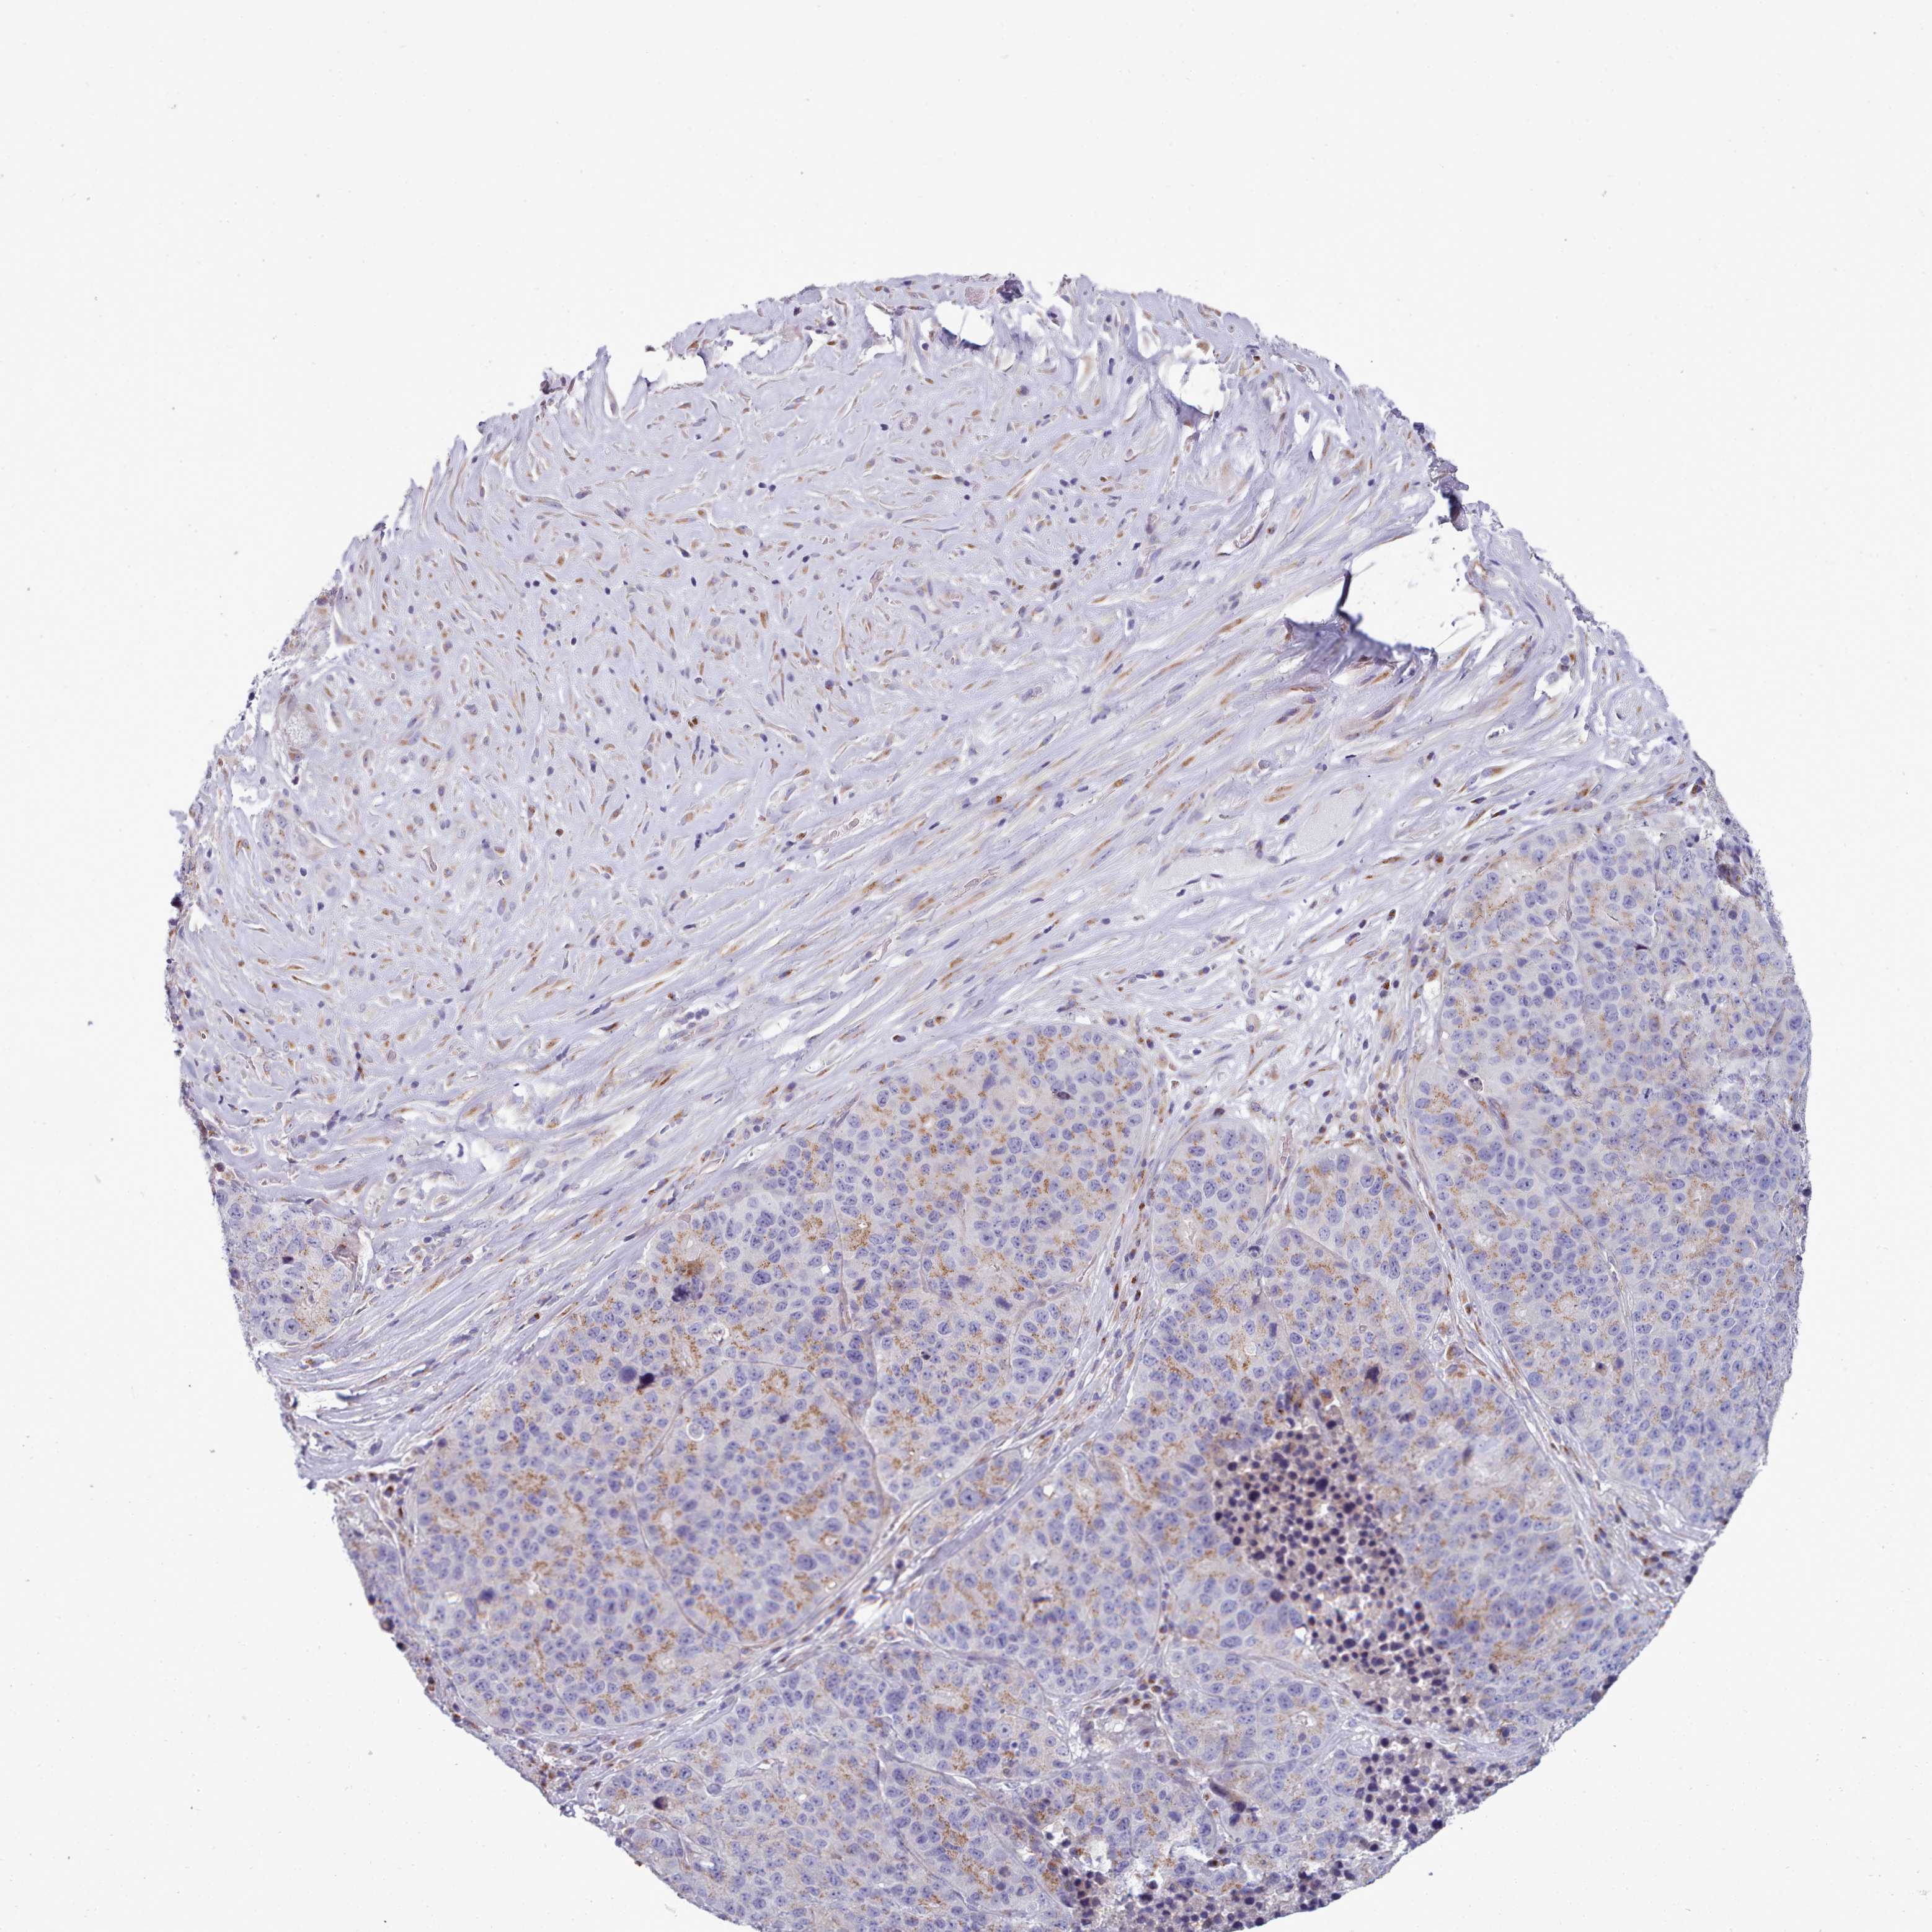

STOMACH CANCER - Protein expressioni

A mouse-over function shows sample information and annotation data. Click on an image to view it in a full screen mode. Samples can be filtered based on level of antibody staining by selecting one or several of the following categories: high, medium, low and not detected. The assay and annotation is described here.

Note that samples used for immunohistochemistry by the Human Protein Atlas do not correspond to samples in the TCGA dataset.

Antibody stainingi

Antibody staining in the annotated cell types in the current human tissue is reported as not detected, low, medium, or high, based on conventional immunohistochemistry profiling in selected tissues. This score is based on the combination of the staining intensity and fraction of stained cells.

Each image is clickable and will lead to virtual microscopy that enables deeper exploration of all samples and also displays staining intensity scores, fraction scores and subcellular localization as well as patient and tissue information for each sample.

Antibody HPA049340

Staining

High

Medium

Low

Not detected

Intensity

Strong

Moderate

Weak

Negative

Quantity

>75%

75%-25%

<25%

None

Location

Nuclear

Cytoplasmic/membranous

Cytoplasmic/membranous,nuclear

Adenocarcinoma, NOS